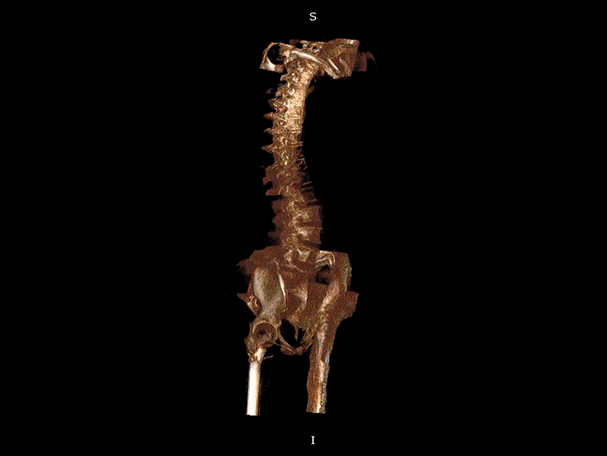

髋关节

VR体绘制重建